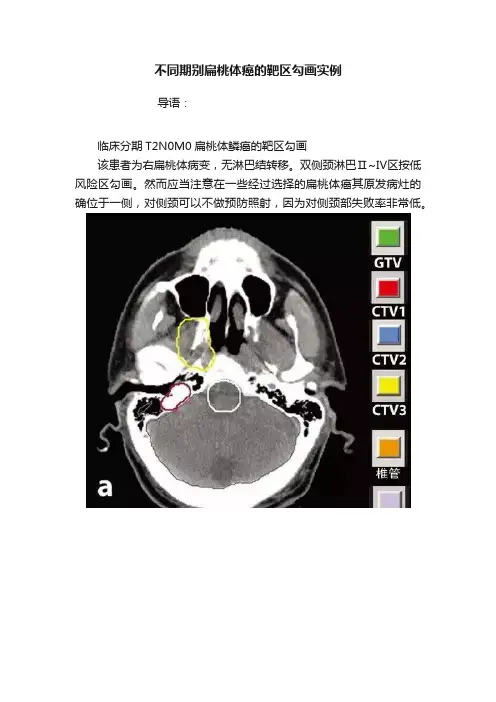

临床分期T2N0M0扁桃体鳞癌的靶区勾画

该患者为右扁桃体病变,无淋巴结转移。

双侧颈淋巴Ⅱ~Ⅳ区按低风险区勾画。

然而应当注意在一些经过选择的扁桃体癌其原发病灶的确位于一侧,对侧颈可以不做预防照射,因为对侧颈部失败率非常低。